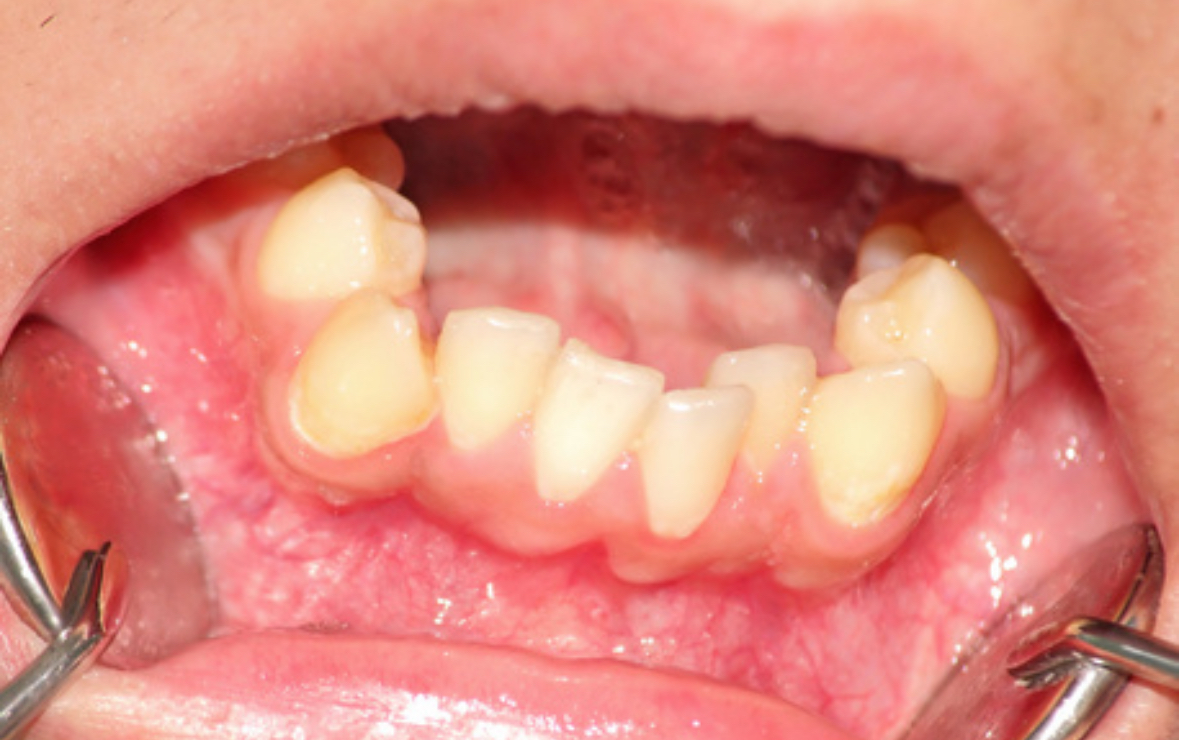

牙齒突出不僅影響美觀,還可能導(dǎo)致口腔功能障礙,如咀嚼困難、發(fā)音不清等問(wèn)題,甚至影響個(gè)人的心理健康和社會(huì)交往。為了提高牙齒突出患者的生活質(zhì)量,以下是珠海鼎植口腔醫(yī)院的一些實(shí)用的建議:

牙齒突出最根本的解決方法是通過(guò)專業(yè)的口腔正畸治療。常見(jiàn)的治療方法包括傳統(tǒng)的金屬托槽矯正、陶瓷托槽矯正、隱形矯正等。選擇合適的矯正方法,可以有效改善牙齒排列,恢復(fù)正常的咬合關(guān)系,提升面部美觀度。